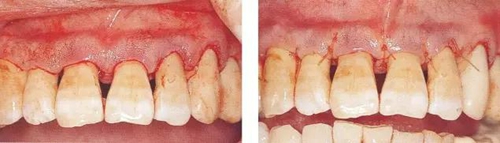

▼圖10-5(左)  利用骨膜分離器進行全厚瓣翻瓣。根面處留存一層薄薄的包含牙周袋內(nèi)緣上皮的組織(頸領(lǐng))。

▼圖10-6(右)  除去牙冠周圍組織的狀態(tài)。將肉芽組織完全去除后,出血變少牙槽骨和牙根的移行部變得明了,徹底清理變得更容易。

▼圖10-7(左)  進行了徹底的SC/RP(潔牙、根面平整)后,將齦瓣復(fù)位。上頜前牙部有審美性要求,因而要盡量減少根面露出的情況下,為了減少切除的組織,將submarginal incision的位置從齦緣處調(diào)整齦緣0.5mm處。

▼圖10-8(右)  縫合后的狀態(tài)。恰當進行切開、翻瓣的話,齦瓣和牙根之間應(yīng)該不會殘留間隙。齦瓣和根面的情況好的話,術(shù)后很少會出現(xiàn)疼痛和出血,治愈也會更快。